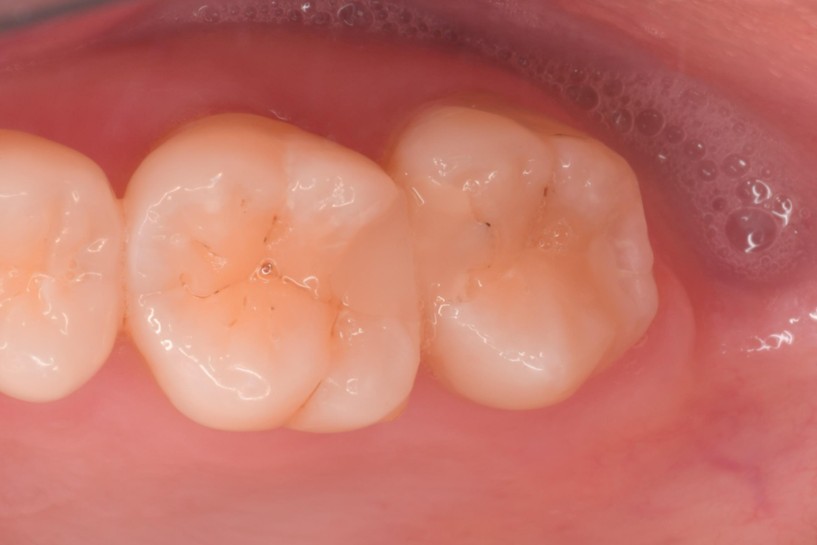

治療前,大臼齒冷熱敏感